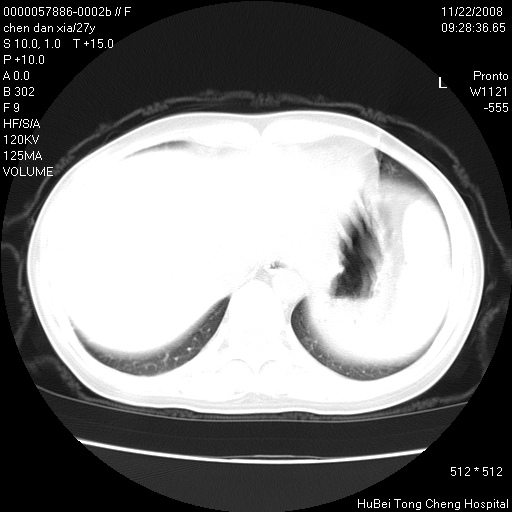

标题: CT16752:F,27Y。发热咳嗽20余天,伴盗汗。 [打印本页]

标题: CT16752:F,27Y。发热咳嗽20余天,伴盗汗。

右下肺见片絮状影,两肺野内分布不均的小结节影,结核并肺内播散可能性大,建议结合实验室检查 .

局部胸膜增厚

右侧前胸壁胸膜局限性肥厚(胸膜炎?)其他的强化观察.

1)考虑两肺感染性病变。2)纵隔淋巴结肿大。